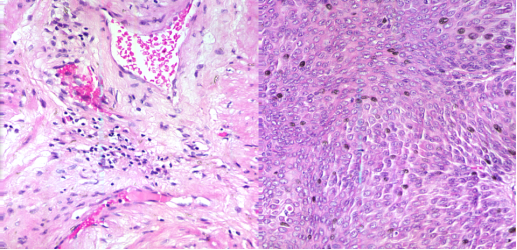

3.1. 顯微高光譜在腫瘤組織檢測的應用

醫學高光譜圖像將二維空間圖片與一維光譜信號合并為一個三維數據立方體。結合光譜和成像技術,醫學高光譜圖像的本質是反映材料以及在分子級別的電磁波下如何吸收和反射光線。它不僅包括豐富的空間信息,更包含許多稱之為光譜特征的連續窄波段,這樣能夠準確地區分不同的血細胞。目前,醫學高光譜成像技術已應用于舌腫瘤、腸道缺血及癌癥、出血性休克、醫療食品安全以及其它診斷學的檢測。

圖2 (a)100X宮頸癌非腫瘤切片 (b)100X宮頸癌腫瘤切片

圖3 左邊:40X膀胱癌非腫瘤切片;右邊:40X膀胱癌腫瘤切片

圖4 腫瘤組織和非腫瘤組織的光譜圖